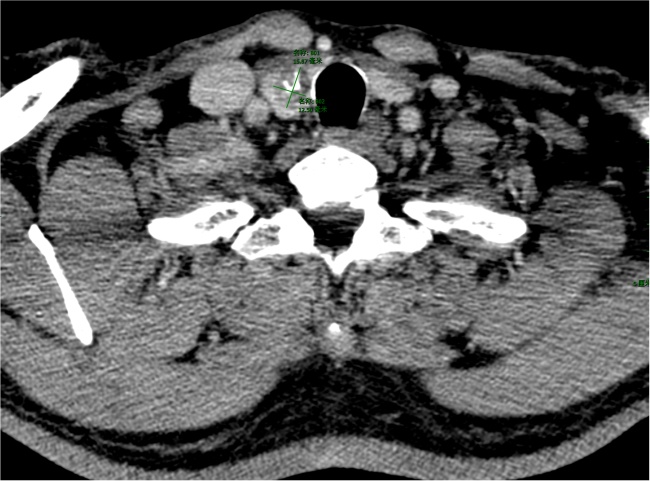

注:甲状腺增强静脉期(a)及相应ROI区域勾画(b)。

Figure 1. CT imaging of a 54-year-old male patient with thyroid

1. 男性54岁甲状腺CA患者CT影像

由2名具有6年以上甲状腺CT诊断经验的放射科主治医师采用联影URP组学软件在CT图像上分别逐层手动勾画ROI (图1图2),然后自动提取影像组学特征,通过组内相关系数(intraclass correlation coefficient, ICC)检验保留ICC ≥ 0.75的特征,依次通过最大相关最小冗杂(max-relevance and min-redundancy, mRMR)及最小绝对收缩与选择算子(least absolute shrinkage and selection operator, LASSO)算法筛选影像组学特征。行LASSO回归分析时,通过10折交叉验证进行特征降维,得到最优超参数λ值,影像组学评分(Radscore)。最终基于随机森林、逻辑回归、支持向量机构建影像组学模型。